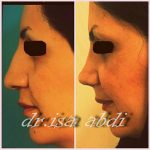

– متخصص جراحی فک , پلاستیک صورت و بینی

جراحی فک , پلاستیک , صورت وبینی

جراحی ترمیمی و زیبایی فک و صورت و جمجمه و گردن